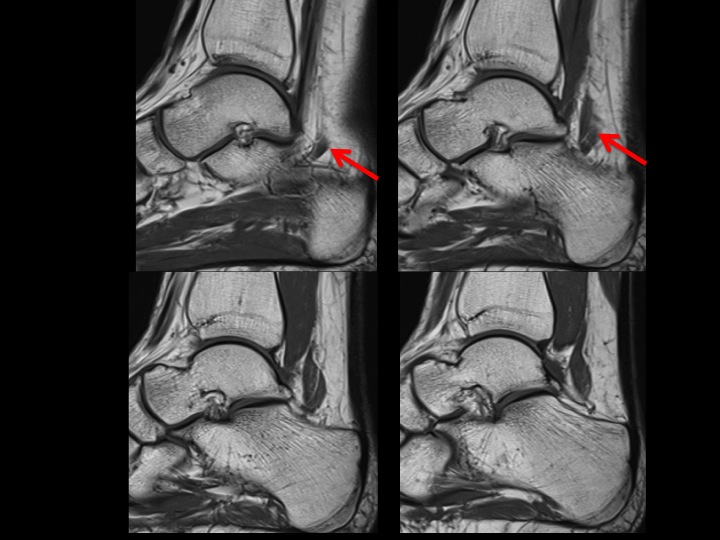

The accessory muscle in question (red arrows) appears to arise from the posterior aspect of the distal fibula. From cranial to caudal it lies lateral then posterolateral to the FHL and inserts onto the quadratus plantae. This does not conform to any of the reported accessory flexor muscles I can find. What would you call it? It shares the same insertion as the FDAL, but does not course superficial to the Posterior Tibial NV bundle. (Did you notice the peroneus quartus? She seems to have too much of everything!) Reference article.